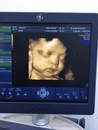

ทีมตุลามาอวดกันหน่อยคะ😁😘 31 w

31ตุลาค่ะ ตอนนี้31วิค1วันคะ